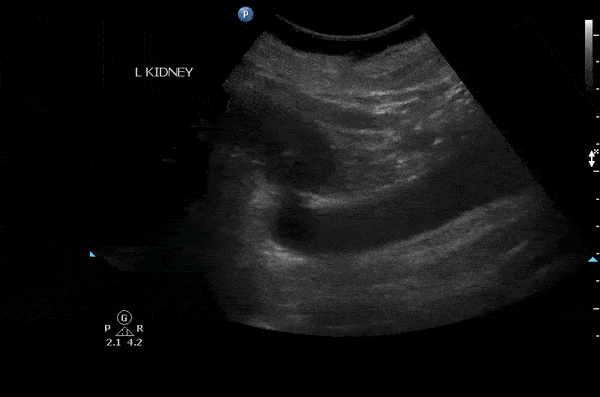

This patient presented with left flank pain. The large anechoic structure had no color flow when doppler was applied. This was a megaureter which can result from VUR, bladder outlet obstruction, idiopathic. In this patient it was known and due to VUR. Image courtesy of Robert Jones DO, FACEP @RJonesSonoEM Director, Emergency Ultrasound; MetroHealth Medical Center; Professor, Case Western Reserve Medical School, Cleveland, OH View his original post here